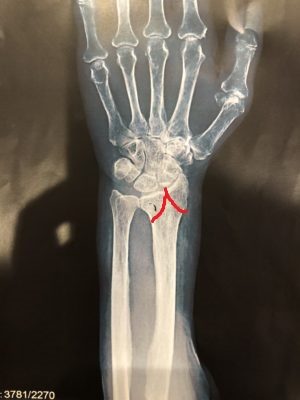

転位はありませんでしたが関節内で骨折していました。

分かりやすく骨折線を描いたものがこちら

今回の骨折の場合は、もし患者様が骨折後に手をついていた場合は

骨片が転位してしまい手術になる可能性があった危険な骨折でした。